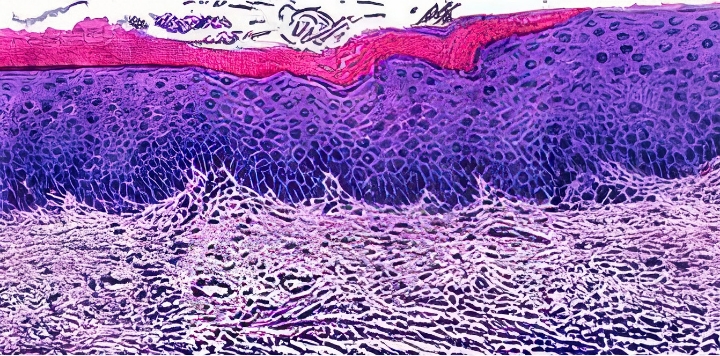

질 조직 정상 수준으로

회복되며 질 건조증 개선

JS트로겐 투여 시, 각화세포층을 포함한

질 조직이 정상에 가깝게 회복